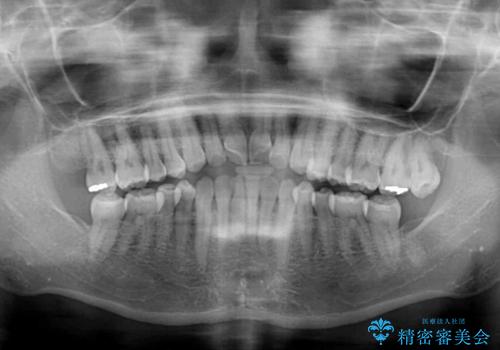

前歯の叢生と切端咬合 インビザラインによる矯正治療

- 前歯のデコボコを気にして来院された患者様です。

上下前歯の先端同士が接触する切端咬合であったため、上顎は歯列を拡大し、下顎はIPR(歯と歯の間を削る)により叢生を解消しながら歯列を小さくすることとしました。

治療前から歯肉退縮が認められ、矯正治療により悪化する可能性が考えられたため、無理のない歯の移動と頻繁な経過観察を行いました。

切端咬合はスムーズに解消され、前歯の負担を軽減させることができました。